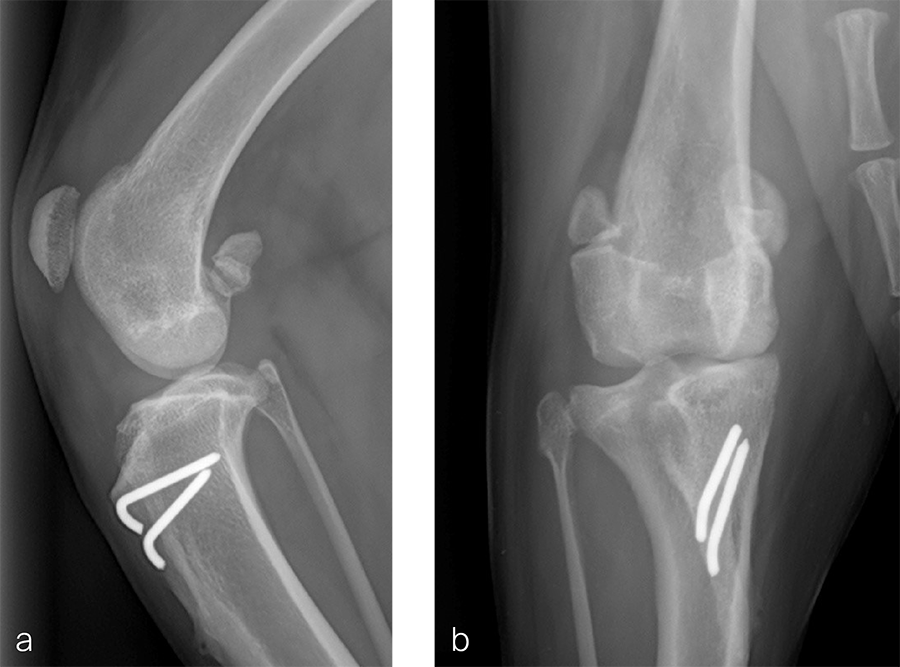

A 1.5 year old spayed female Appenzell Cattle Dog weighing 29 kg presented for a second opinion after two previous surgical procedures (Fig 7 and Fig 8) to address a traumatically induced medial patellar luxation. Orthopedic examination and preoperative radiographs revealed a grade 3/4 medial patellar luxation (Fig 8). Femoral varus was documented (aLDFA 104°; normal 92–96°) by CT scan (Fig 9 ). The planned correction was a 10° lateral closing wedge ostectomy, with concurrent sulcoplasty. Click here to read through the detailed surgical procedure.

Fig 8a–b Revision surgery performed to address persistent patellar luxation. A tibial tuberosity transposition was performed to realign the insertion of the patellar tendon without addressing femoral deformity. Radiographs were obtained two months postoperatively. The patellar luxation persists despite transposition of the tibial tuberosity.